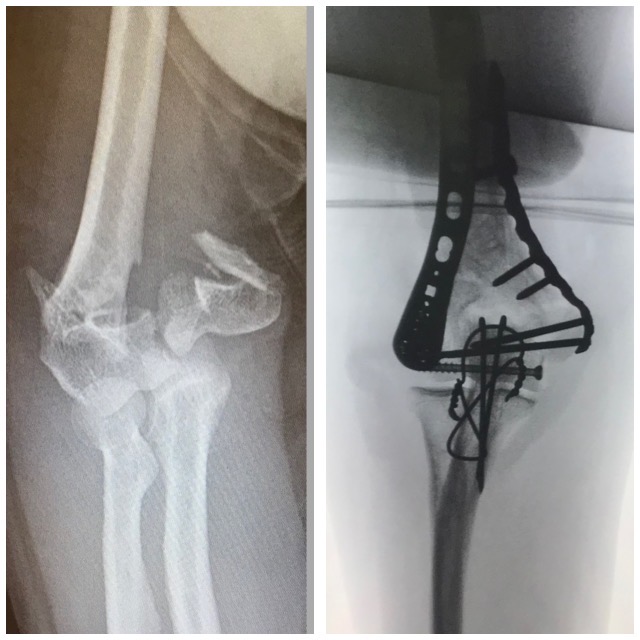

Rannemurtuma

Ennen – jälkeen